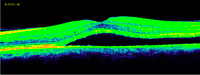

3-5. Tanto el EMQ como el EMD pueden asociarse a DRS (

Tabla 2 y

Figura 4,

Figura 5,

Figura 6 y

Figura 7).

Tabla 2. Características de OCT de los 3 subtipos de edema macular.

Figura 4. Edema macular quístico (EMQ).

Figura 5. Edema macular difuso (EMD).

Figura 6. Desprendimiento de retina seroso (DRS) en una paciente con uveítis asociada a enfermedad de Behçet.

Figura 7. Desprendimiento de retina seroso subfoveal asociado a edema macular quístico en una paciente con coroidopatía tipo Birdshot.